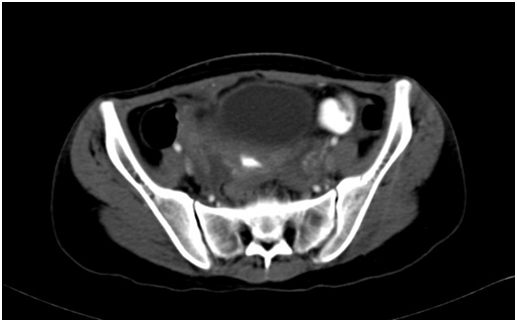

Computed tomography with oral contrast study showed Ileo-uterine fistula . Patient was taken up for exploratory laparotomy. Intra operatively ileo-uterine fistula was noted . A 2 cm dense adhesion between distal ileum and fundus of uterus was noted. Adhesiolysis was done and edges of uterine rent were freshened and approximated with 2-0 polyglactin interrupted sutures. Loop ileostomy was done. She was discharged on post operative day 10.

Figure 1. Computed tomography of pelvis with oral contrast shows contrast filled ileum looping around the uterus.

Figure 2. Oral contrast in the endometrial cavity consistent with ileo uterine fistula.